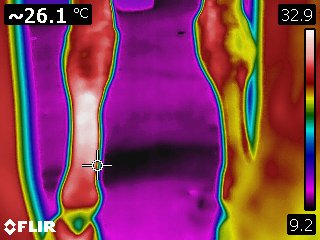

Infrared thermography is a dynamic modality providing a detailed, real-time image of the physiology of an area. It also provides an evaluation of the intensity and distribution of the heat associated with a tendon or ligament. As such, it is a method for specifically and repeatedly monitoring the extent of initial damage and to follow the repair process. Because thermography can accurately and repeatedly differentiate between various areas of tendon within a larger damaged area, sequential scans can provide useful information for treatment and in the repair process, as well.

Courtesy Kenneth Marcella, DVM

Courtesy Kenneth Marcella, DVM

Courtesy Kenneth Marcella, DVM